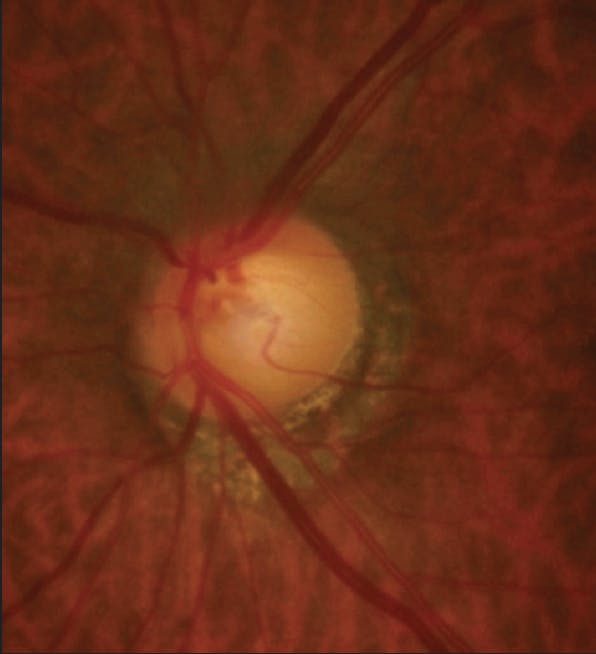

A 59-year-old Hispanic man was referred to me for a glaucoma evaluation after his optometrist detected a disc hemorrhage in the patient’s right eye. He had no significant past medical history or ocular history and no family history of glaucoma. BCVA was 20/20 OU, and the refractive error was around -3.00 D of sphere in each eye. CCT was 536 µm OD and 538 µm OS. Cup-to-disc ratios were 0.8 OD and 0.85 OS. A resolving disc hemorrhage and inferior thinning of the retinal nerve fiber layer (RNFL) were observed in the right eye (Figure 1), and peripapillary atrophy and inferior thinning of the RNFL were observed in the left eye (Figure 2). VF testing showed a relatively stable field in the left eye (Figure 3A) but there was a mild nasal step (Figure 3B) and corresponding focal loss of RNFL on OCT in the right eye (Figure 4). Goldmann IOPs were 13 mm Hg OD and 14 mm Hg OS.

Figure 1. A resolving disc hemorrhage and inferior thinning of the RNFL were observed in the patient’s right eye.

Courtesy of Davinder S. Grover, MD, MPH